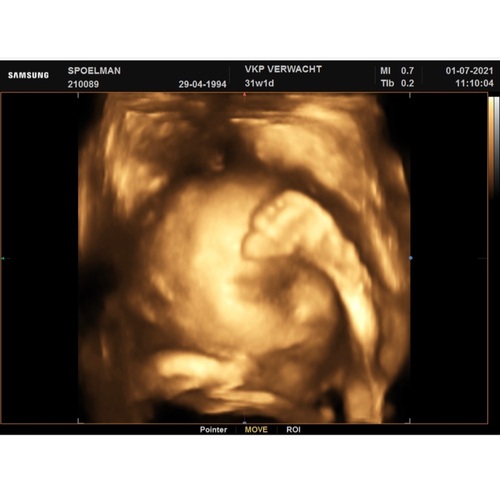

Ik heb twee keer een 4D echo gedaan, met 24 weken en met 28 weken (foto).

Vond het echt fantastisch, ook om het verschil te zien tussen 24 en 28 weken. Hoeveel vetjes erop het gezicht bij zijn gekomen.

Hij lijkt echt op mijn vriend!